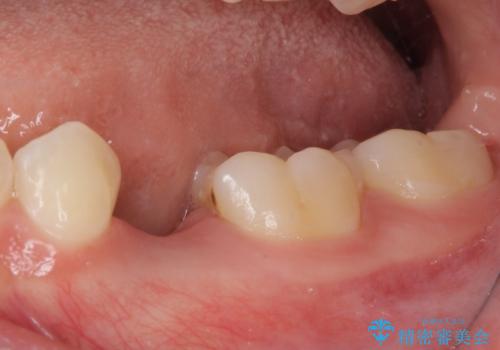

- 前歯の叢生と、奥歯の咬み合わせの悪さを気にして来院された患者様です。

左下には後続永久歯の欠損した乳歯が残存しており、叢生を相まって咬合関係が乱れていました。

乳歯は抜歯し、インビザラインにて矯正治療を行いながら、並行してインプラントによる補綴治療を行うこととしました。